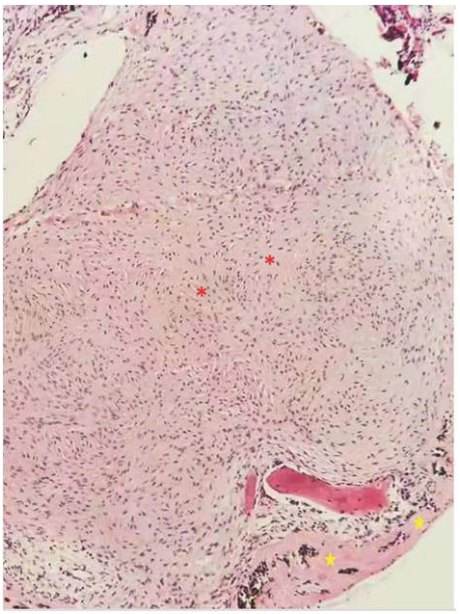

Figure 3 Histopathological analysis of a subfoveal nodule removed from another eye (Patient 3) with Coats' disease.

H&E staining was performed with hematoxylin and eosin (X126). The red asterisks denote myofibroblastic hyperplasia in the tissue. The yellow pentagrams denote hyalinization of the tissue.

Figure 1 shows the presurgical fundus image and postoperative fundus images of patient 3. SD-OCT image at the level of the fibrotic nodule at the presentation showed a hyperreflective, sharply demarcated subfoveal lesion associated with a posterior shadowing effect, moderate retinal layer disorganization and retinal thickening, with abrupt elevation of retinal layers by the underlying hyperreflective nodule. Histopathological examination of the excised tissue revealed that the subfoveal nodules were fibrous tissue, which was composed mainly of fibroblasts and myofibroblasts. In these six nodules, 5 of them have cholesterol fissures, 4 have foreign body giant cells, all of them have chorionic cells and myofibroblastic hyperplasia. In addition, 3 of the 6 patients have ossified tissue in their subfoveal nodules.These features were associated with ossification and hyaline degeneration (Figures 2 and 3).